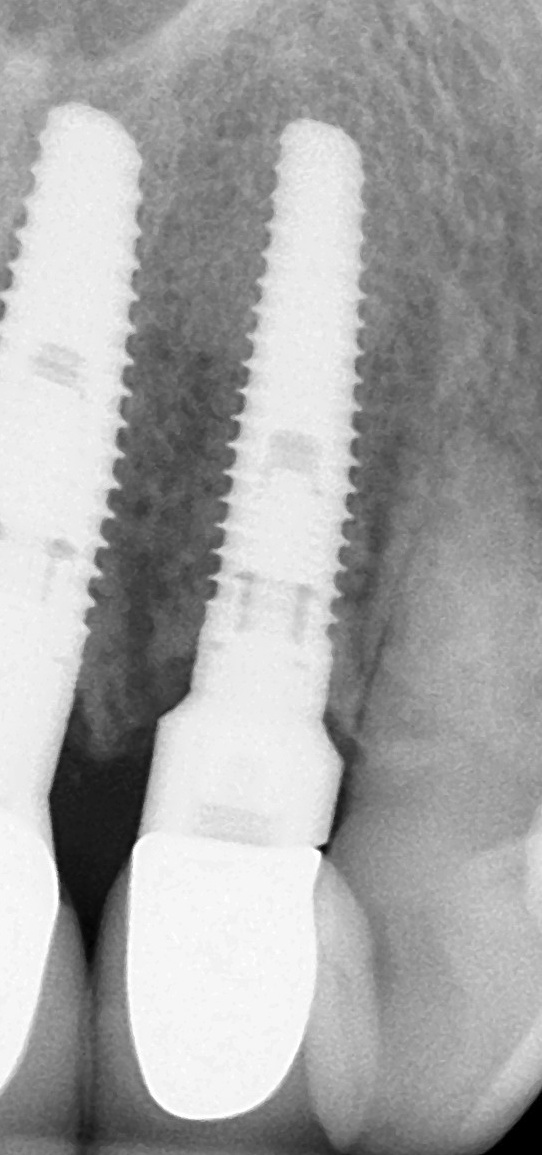

Fig 1. This implant was placed in March 2006. Peri-implantitis was clinically evident in April 2008, with bleeding on probing, suppuration, and increasing probing depth.

Figure 1